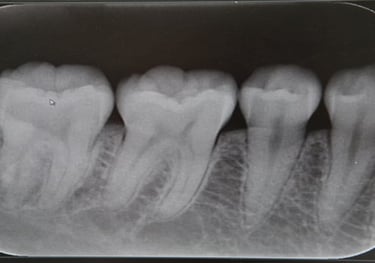

RADIOGRAFIA INTERPROXIMAL